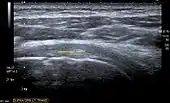

Longitudinal ultra sonography of the supraspinatus tendon